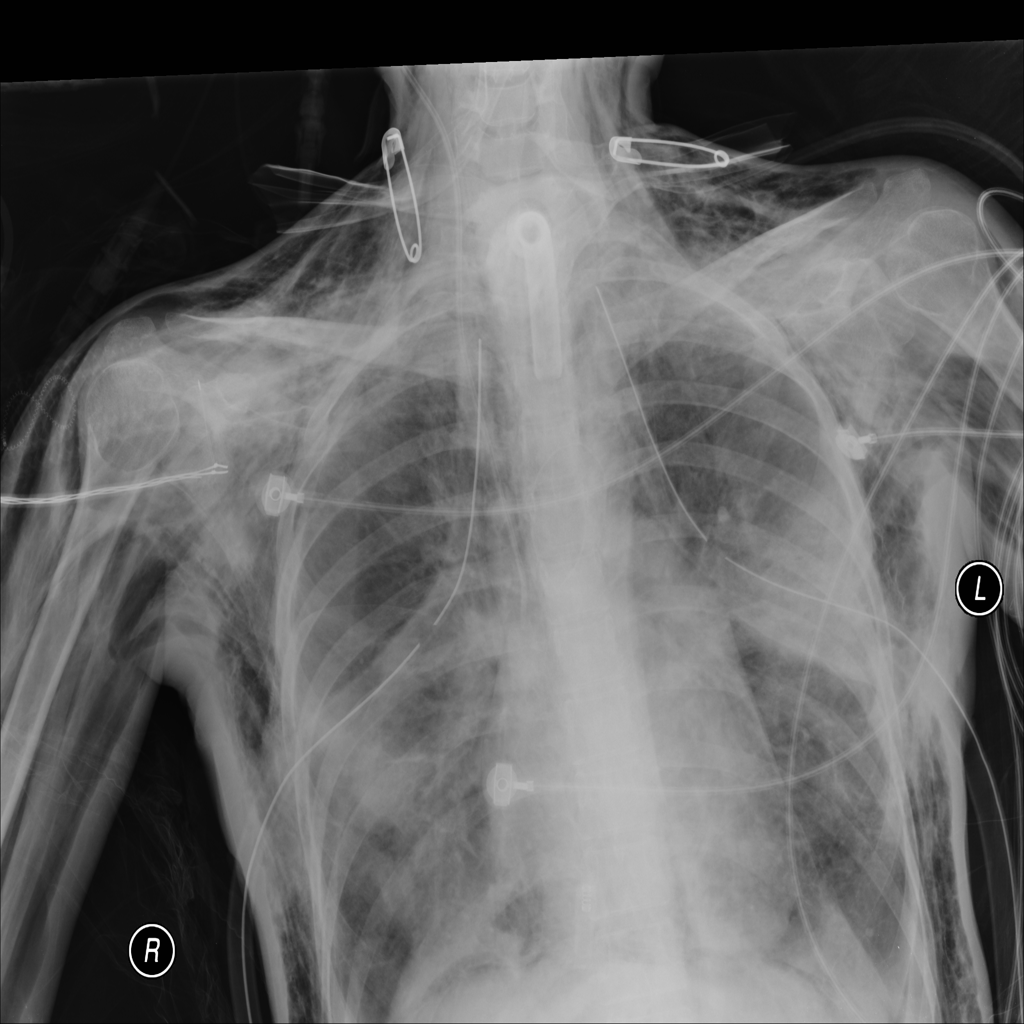

PAT-B0DB · IMG-003Emphysema

PAT-B0DB · IMG-003

PA